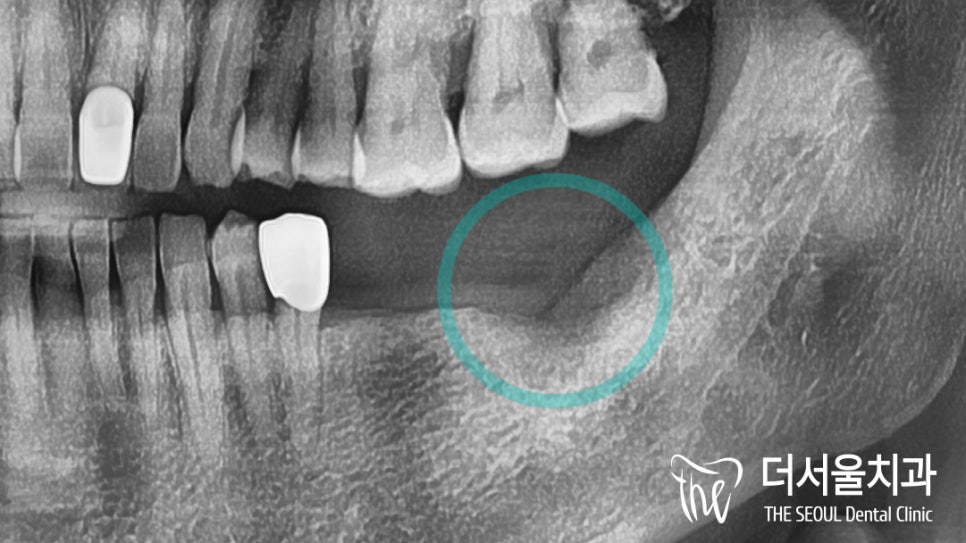

좌측이 원인이란 생각이 들었는데요.

자세히 살펴보니 지대치 치근 부위로

심한 손상이 나타나 있었습니다.

*염증으로 인해 치조골 소실이 나타나

골이식재를 동반하여 식립하기로 함.